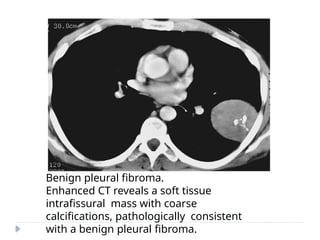

Benign pleural fibroma.

Enhanced CT reveals a soft tissue

intrafissural mass with coarse

calcifications, pathologically consistent

with a benign pleural fibroma.

SOLITARY FIBROUS TUMOROF PLEURA (SFTP)  Also known as localized fibrous tumor or localized pleural mesothelioma.  45- 60 yrs  Most of the tumors are benign; 20 % cases – malignant.  Arises from visceral pleural in 80 %  ON IMAGING :  Soft tissue pleural-based neoplasm  Areas of necrosis, hemorrhage, and cystic changes.  Calcification may be seen in up to 26% of cases.  Heterogeneous enhancement is seen post-contrast.  On magnetic resonance imaging (MRI), hypointense solid mass is seen on T1- and T2-weighted images. Necrosis and cystic degeneration changes show high T2 signal intensity.

Benign pleural fibroma. EnhancedCT reveals a soft tissue intrafissural mass with coarse calcifications, pathologically consistent with a benign pleural fibroma.